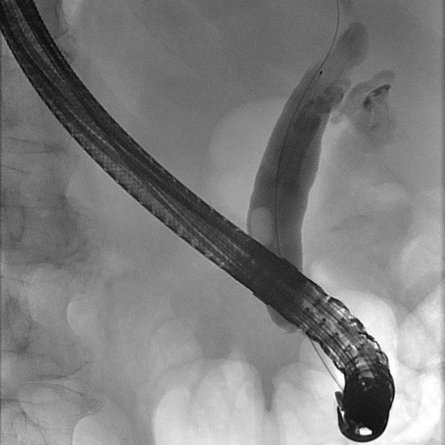

Eine Patientin stellte sich bei uns mit Beschwerden durch Gallensteine im Gallengang vor. Aufgrund der vorangegangenen Magenbypass-Operation war die Papille auf konventionellem endoskopischem Weg nicht erreichbar. Nach ausführlicher Aufklärung entschieden wir uns gemeinsam mit der Patientin für ein modernes, minimal-invasives Verfahren: die sogenannte EDGE-Prozedur (Endoscopic Ultrasound-Directed Transgastric ERCP).

Hierzu wurde zunächst mithilfe der Endosonographie (Ultraschall von innen) der ausgeschaltete Magenanteil aufgesucht. Dieser wurde gezielt punktiert und die korrekte Lage unter Röntgendurchleuchtung mit Kontrastmittel überprüft (Abbildung 1).